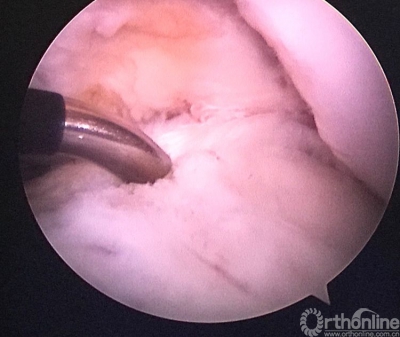

关节镜检查见重建的韧带已经消失。

原来重建的ACL胫骨隧道内口偏前(等离子刀头所指处)。